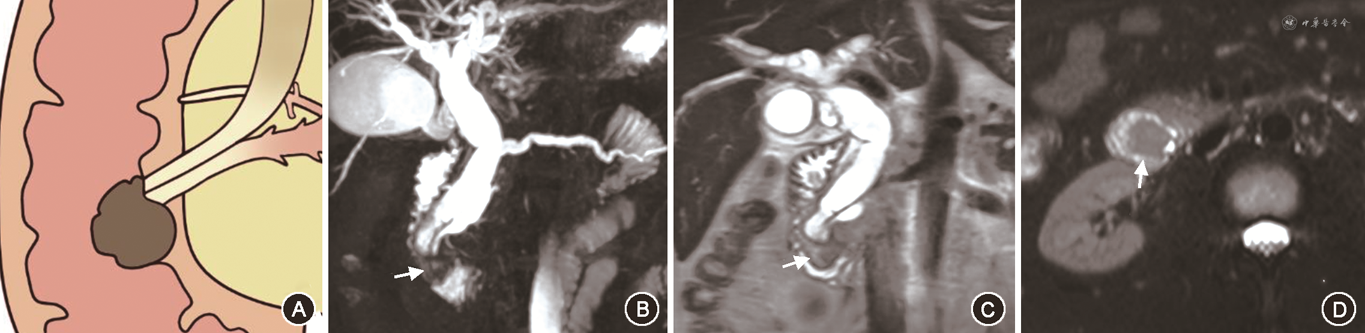

在对有意义单因素指标的分析中,笔者将PAC的MRI征象进行总结,最后归纳为十二指肠乳头结节型、胰腺肿块型、胆总管壁增厚型、壶腹部肿块型及胆总管腔内结节型5种表现类型。十二指肠乳头结节型MRI征象为位于十二指肠腔内的病灶,多为等信号,在十二指肠乳头形成突入腔内的结节,MRCP上胆总管及胰管扩张呈双管征,胰胆管角度较小,双管征走行呈平行或聚拢(图1)。胰腺肿块型MRI征象为胰腺内低信号肿块,MRCP上胆总管及胰管单独或同时狭窄截断可分别出现双管征、三管征、四管征,截断胰管周围可见扩张侧支,肿块引起胰胆管角度增大,管征呈分离走行(图2)。胆总管壁增厚型MRI征象为胆总管远段管壁增厚,近段胆管扩张,MRCP上胰管较少扩张,近段扩张胆管、梗阻下方远段胆总管与胰管呈三管征(图3)。壶腹部肿块型在MRI图像上表现为壶腹部跨壁生长的肿块,可与胰腺、十二指肠肠壁分界不清,但较少使十二指肠乳头表现为结节型,MRCP管征多为双管征(图4)。胆总管腔内结节型在MRCP图像上远端胆总管内见结节样充盈缺损伴胆道梗阻,远段胆总管、近段扩张胆总管及胰管呈三管征(图5)。

Fisher精确概率法结果显示,IPAC与PPAC在MRI影像5分型的差异具有统计学意义(P<0.001)(表4)。经调整检验水准后的 Bonferroni 法两两比较结果显示,十二指肠乳头结节型与胰腺肿块型、胆总管壁增厚型及壶腹部肿块型的差异均具有统计学意义(均P<0.005)。IPAC多表现为十二指肠乳头结节型(15/21,71.4%)(图1),PPAC更多表现为胰腺肿块型(18/38,47.4%)、胆总管壁增厚型(9/38,23.7%)或壶腹部肿块型(9/38,23.7%)(图2, 3, 4),IPAC(2/21,9.5%)与PPAC(0,0)均较少表现为胆总管腔内结节型(图5)。